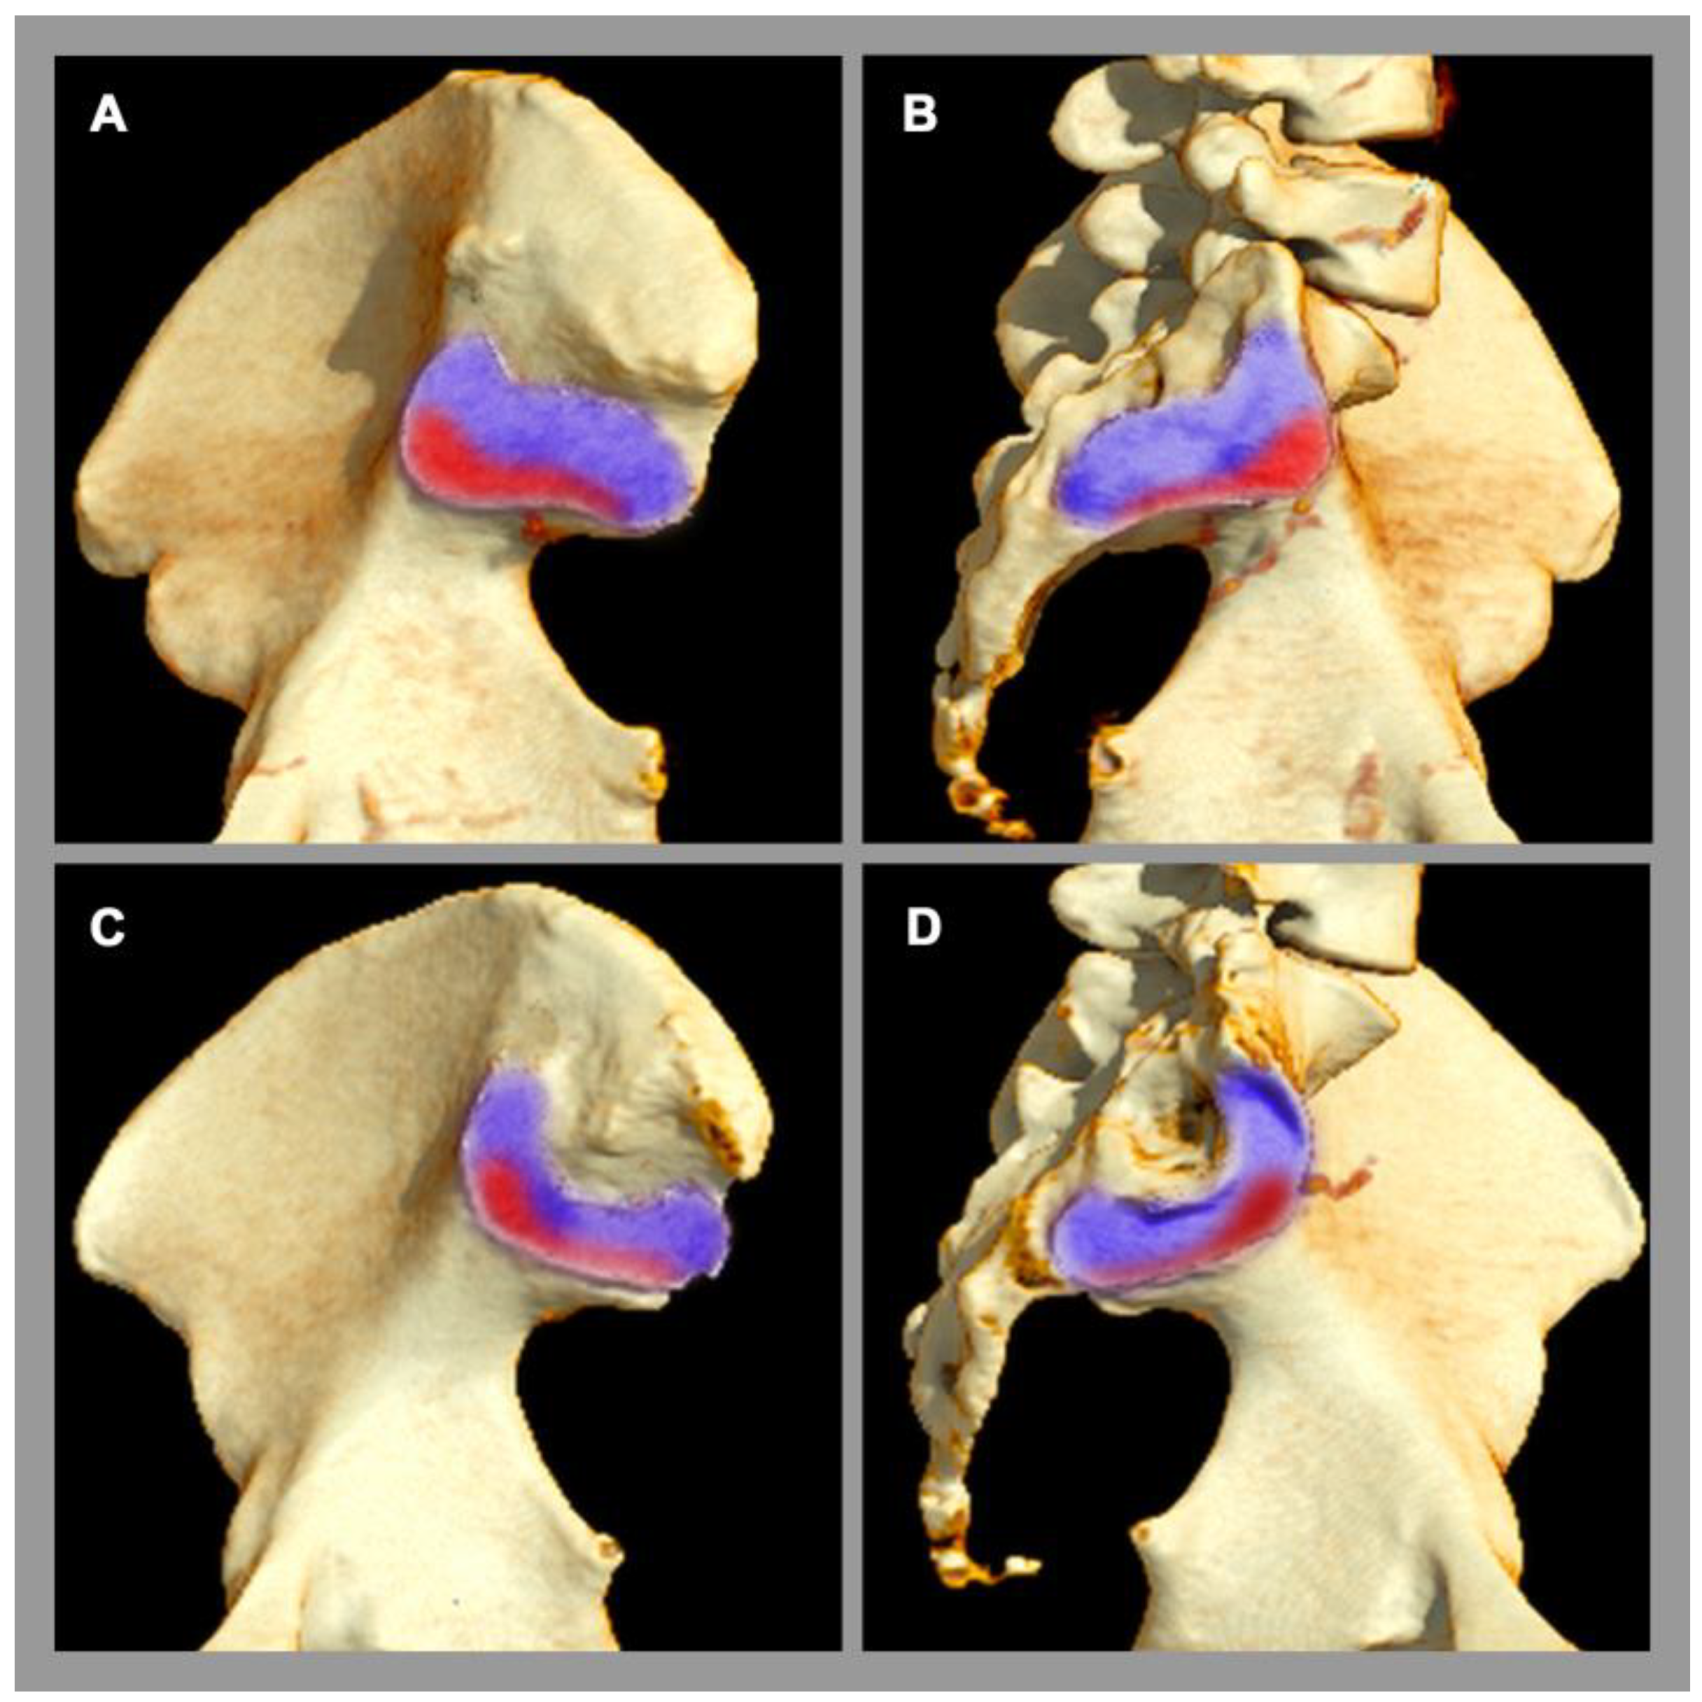

Osteitis condensans ilii is a frequent pathology of the SIJ [5], which is classified as a non-inflammatory disease. Its origin is attributed to mechanical stress and imbalance across the SIJ, e.g., during pregnancy and childbirth [2], causing a chronic stress response. Clinically, affected patients present with chronic back pain, which typically begins before the age of 45 [5]. Osteitis condensans ilii is significantly more common in women than in men, possibly due to the different biomechanical properties of the SIJ and flexible ligamentous structures in the female pelvis [5], especially concerning delivery. The typical imaging finding at the sacroiliac joint is sclerosis and its specific distribution pattern in the anterior and inferior part of the SIJ with a typical triangular shape (also called “hyperostosis triangularis ilii”) [5]. In addition, bone marrow edema can also be seen in osteitis condensans ilii, but this is not specific, since other factors, such as sporting activities, can also lead to bone marrow edema in the SIJ in the region of mechanical stress [54,55], see Figure 3.

Figure 3.

Sacroiliac joint load zones. 3D computed tomography reconstruction. (A,C) Lateral view of the ilium. (B,D) Lateral view of the sacrum. Male pelvis (A,B). Female pelvis (C,D). There are sex differences in the distribution of the load zone (red area) with respect to the rest of the joint surface (purple area). In women, the center of gravity is more ventrally located.

In the diagnostic process of degenerative conditions of the SIJ, naturally occurring aging should always be considered. These imaging lesions are to be regarded as a consequence of repetitive, inappropriate biomechanical stress, which is accompanied by joint wear and may result in lower back pain. Besides patchy small-sized focal spots of bone marrow edema, sclerosis, and osteophytes are typical findings, but their distribution pattern in the general population differ between the sexes: In men, the degenerative changes are mainly localized in the ventral part of the SIJ, whereas in women they are more likely to be found ventrally and dorsally [6,56]. In addition, a different age distribution is also evident, where degenerative changes in women show an early peak between 45 and 54 years of age, whereas, in men, a steady increase in degenerative lesions of SIJ with increasing age has been shown [6]. Furthermore, SIJ degeneration in imaging is associated with degenerative changes of the lumbar spine in men but not in women [57].